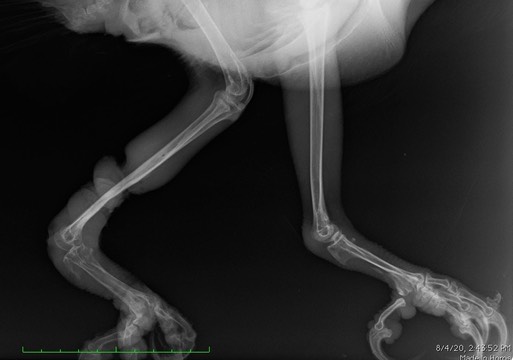

The damage to both bone and soft tissue is visible on the radiograph. The injured leg is on the left.